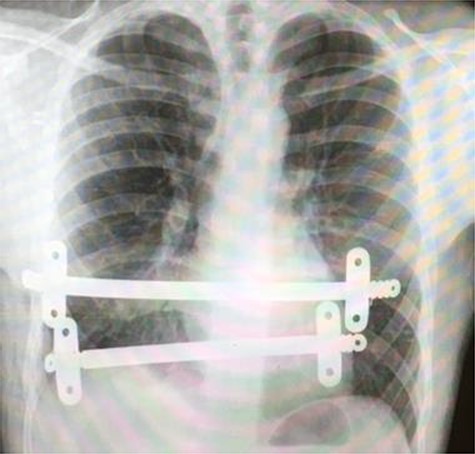

Postoperative chest X-ray following initial Nuss procedure, showing both substernal bars inserted to elevate the depression caused by pectus excavatum.

The patient underwent video-assisted thoracoscopic surgery (VATS) and the modified Nuss- procedure for the surgical correction of his PE. The primary incision was 0.5 cm long along the anterior axillary line of the right lateral chest in the second intercostal space. A 5-mm zero-degree thoracoscope was used to provide clear visualization. An additional 2-cm incision was made, 10 cm underneath the previous incision, where the bar introducer and an 11-inch bar were inserted for correction of the PE. This bar was secured using one stabilizer on each side. An additional second 9-inch Nuss bar was inserted inferior to previous bar with one stabilizer on each side. The procedure was uneventful, and a chest X-ray was performed to confirm adequate substernal bar placement (Fig. 1).